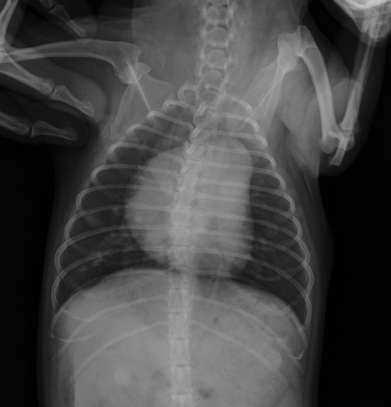

Interstitial pattern

aorta and vena cava is blurry

VD